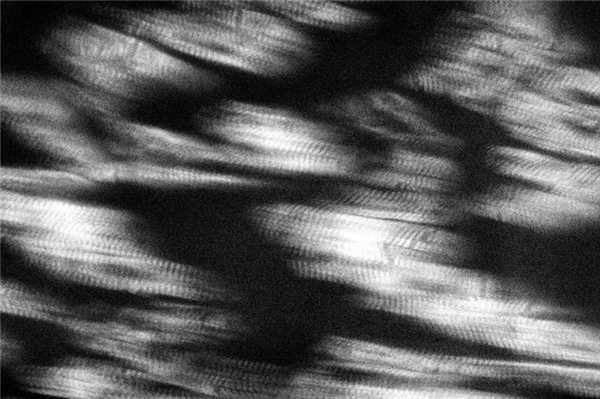

У погибших от странгуляционной механической асфиксии (СМА) вследствие полного повешения с наложением петли на передней поверхности верхней трети шеи и заднебоковым расположением узла исследование микропрепаратов в поляризованном свете установило наличие распространенных субсегментарных контрактур в левом и правом желудочках сердца (рис. 5). Рисунок 5. Распространенные субсегментарные контрактурные повреждения и зоны релаксации кардиомиоцитов при смерти от странгуляционной механической асфиксии. Поляризационная микроскопия. Ув. 640. В левом желудочке они чаще всего встречались в интрамуральных отделах, а в правом наиболее часто отмечались в субэндокардиальных зонах, реже в интрамуральных и еще реже в субэпикардиальных отделах. В обоих желудочках распространенные субсегментарные контрактуры чередовались с зонами релаксации сердечных мышечных волокон и маркерами фибрилляции желудочков. Исследование перикардиальной жидкости выявило повышение содержания глюкозы, калия, магния и кальция, снижение содержания натрия [32—34].